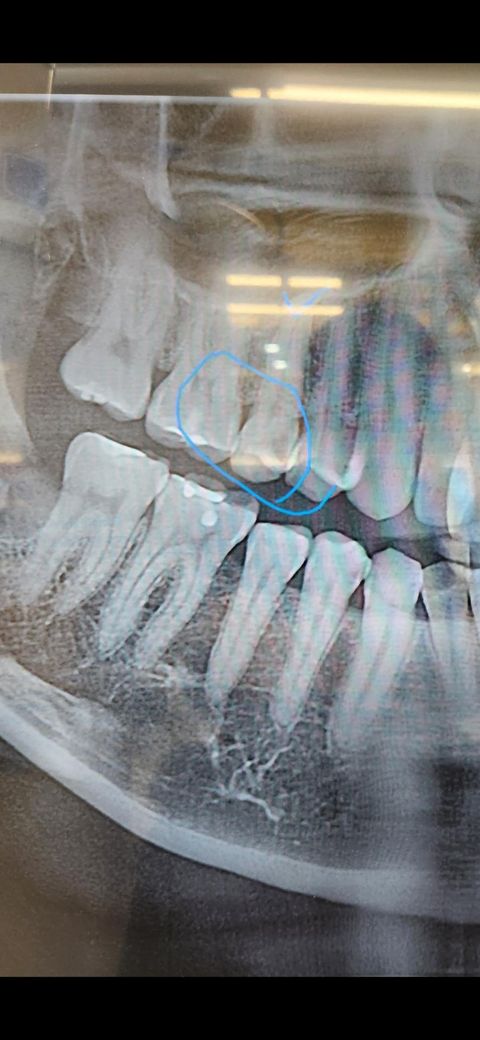

치아에 구멍이 있는 상태이고 통증은 없는 상태 입니다.

검진 받은 곳 의사쌤 말로는 충치가 심해서 레진으로는 안되고 신경치료 후 크라운해야 한다고 합니다.

일단은 엑스레이상으로 충치가 깊습니다 엑스레이는 보통 실제 충치보다 적게 보이는 경우가 많습니다 아마 신경치료 가능성이 매우 높지만 일단 간접치수복조의 개념으로 레진으로 해보고 증상지켜보는식으로 할 순 있습니다